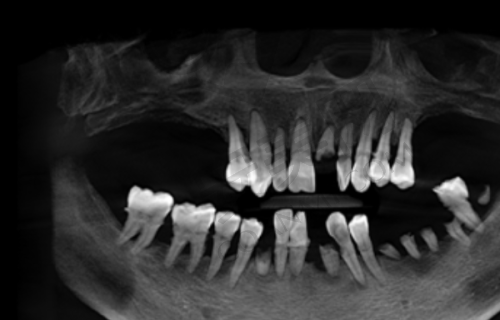

在牙齿种植方面,优佳贝口腔同样表现出色。医院引进了国内外新型的口腔诊疗设备,如数字影像系统、微痛麻醉技术等,确保治疗的精细性和可靠性。种植总监梁照忠院长在种植牙方面具有较高的技术水平,能够接诊复杂的种植手术,如植骨手术、上颌窦内外提升术等。